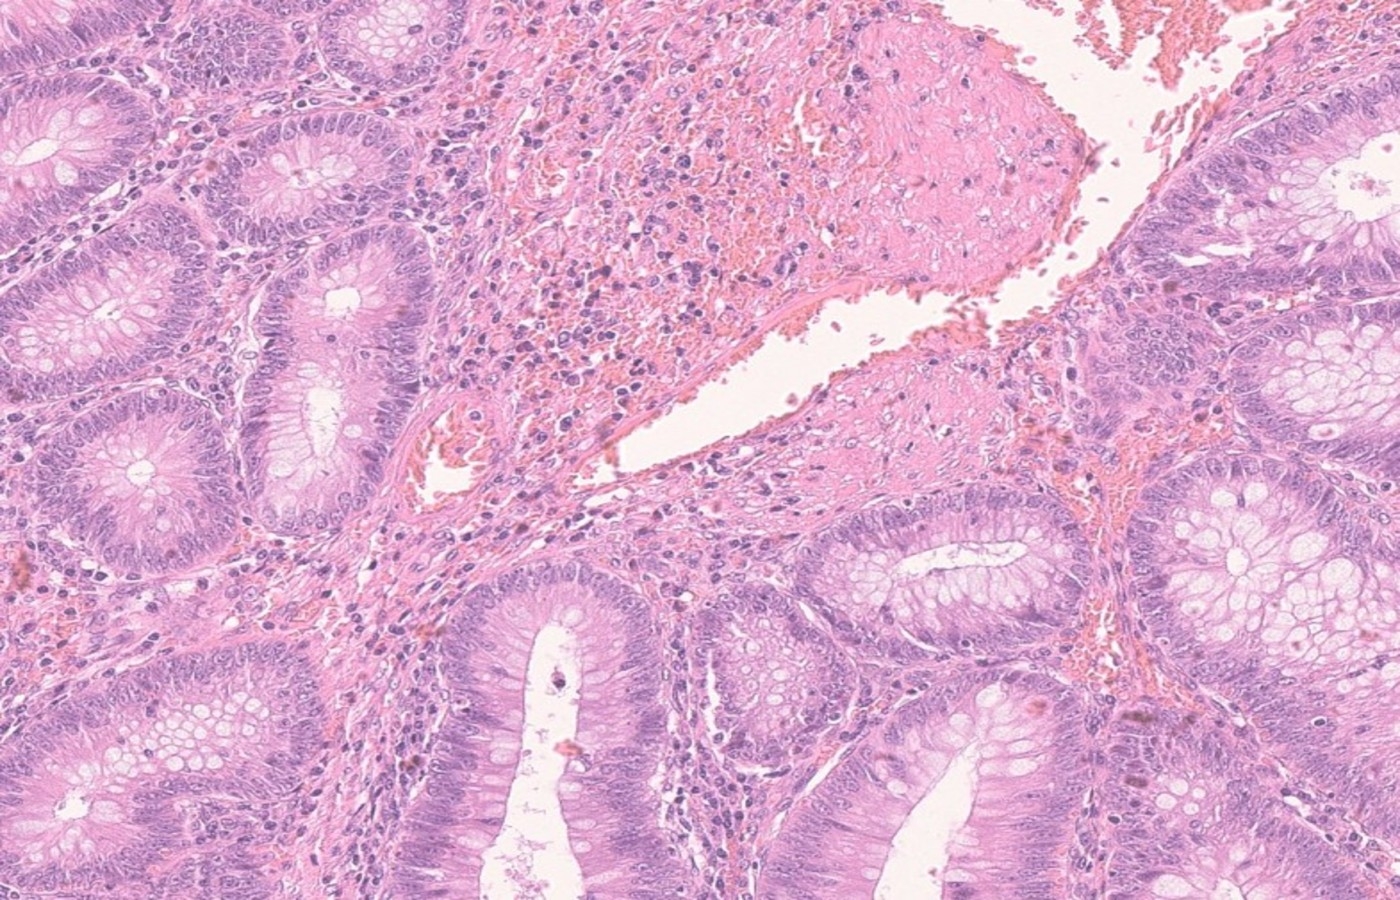

H&E stain of colonic polyp

The University of Glasgow, in collaboration with the NHS and industry, is leading a £3.37m project to transform bowel cancer screening in the UK by developing a risk stratification tool that uses artificial intelligence to predict which patients will develop future polyps and tumours.